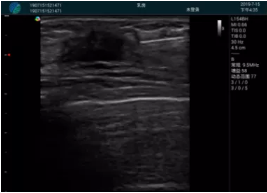

清晰顯示腺體內(nèi)低回聲快影,邊界清晰,包膜較光滑

確定進(jìn)針路徑并實(shí)時(shí)監(jiān)測(cè)抽吸針與腫塊位置關(guān)系

抽吸針進(jìn)入腫塊內(nèi)部進(jìn)行旋切

抽吸過程中可見腫塊明顯縮小,并根據(jù)腫塊位置改變針道位置

抽吸旋切后再進(jìn)行超聲復(fù)查,原腫塊區(qū)域未見殘留組織及出血